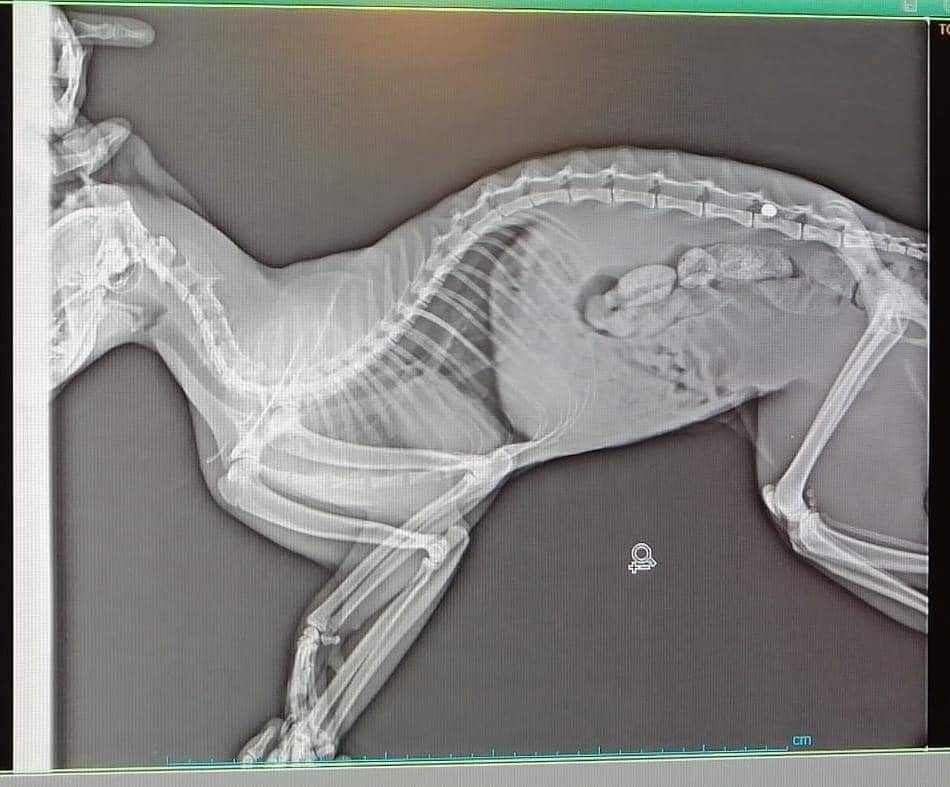

Muğla'nın Bodrum ilçesinde yaralı halde bulunarak tedavi altına alınan kedinin röntgeni şok etti. Omuriliğinde kurşun olduğu ortaya çıkan kedi ameliyat için İstanbul'a gönderilecek.

Edinilen bilgiye göre Torba Mahallesi'nde arka ayakları tutmayan bir kedi gören Şükran Şahin ve Şule Teker isimli hayvanseverler kediyi Hayvan Hastanesi'ne getirdi. Sırtında yarası olan ve yürüyemeyen kedinin röntgeninin çekilmesinin ardından hayvanın silahla vurularak yaralandığı ortaya çıktı. Röntgende kedinin omuriliğine saplanmış kurşun dikkati çekti. Kedi, kurşunun çıkarılabilmesi için İstanbul'a gönderilecek. Kurşun çıkarıldıktan sonra balistik inceleme yapılacağı bildirildi.